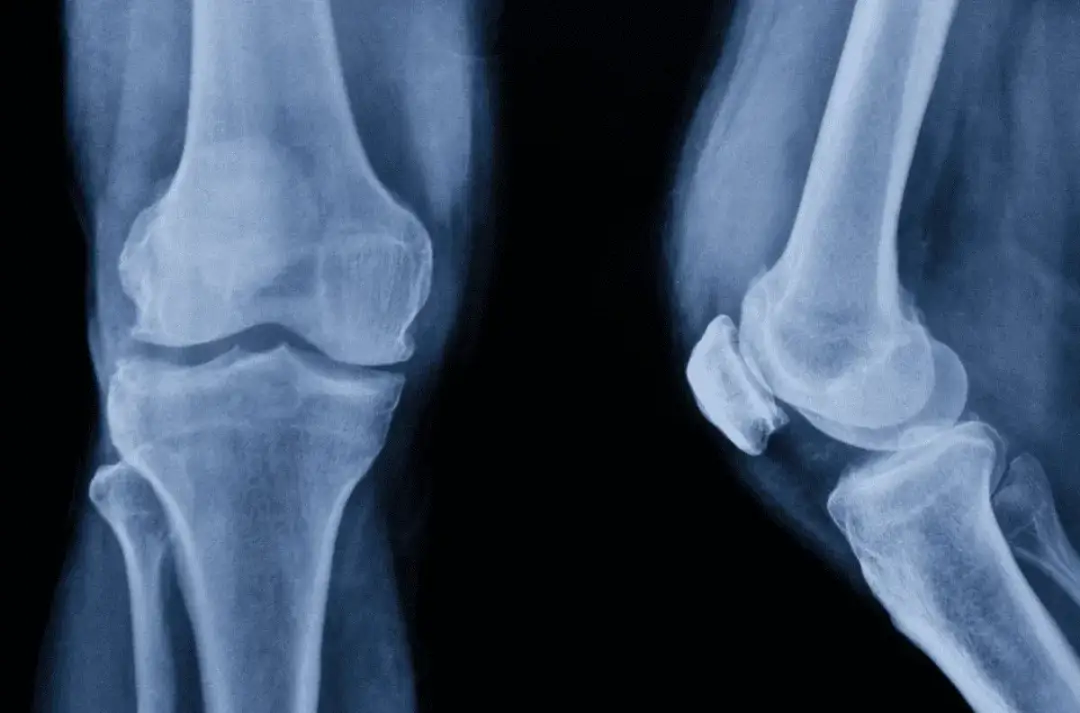

Kolano jest jednym z największych i najbardziej złożonych stawów w ludzkim ciele. Składa się z wielu ważnych elementów, które współpracują ze sobą, umożliwiając prawidłową funkcję i ruch. Podstawowymi składnikami anatomii stawu kolanowego są kości, więzadła, chrząstki stawowe, mięśnie, naczynia krwionośne oraz układ nerwowy.

Kolano łączy dwie główne kości: kość udową (femur) i kość gołeni (piszczel). Te dwie kości spotykają się w stawowym połączeniu, tworząc przestrzeń wypełnioną płynem stawowym i chrząstką stawową. Chrząstka ta pokrywa końce kości, umożliwiając płynny i bezkonfliktowy ruch, jednocześnie amortyzując obciążenia.